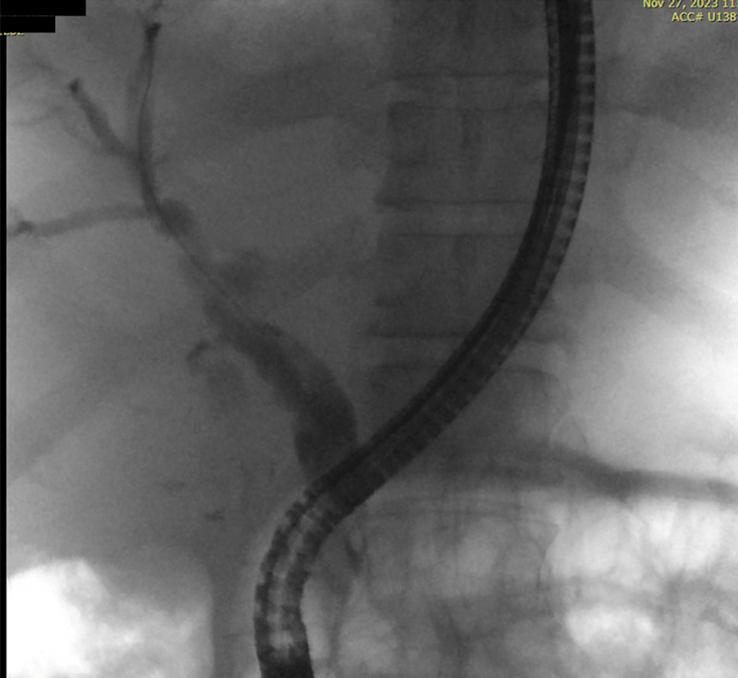

CASE REPORT

This is an unusual case of a 54-year-old male who presented with acute cholecystitis complicated by haemobilia and Mirizzi-like obstruction, in the setting of cystic artery pseudoaneurysm rupture. Initially, urgent transcatheter angiographic embolization of the cystic artery was performed to achieve hemodynamic stability. However, a triphasic computed tomography (CT) scan revealed the first attempt was unsuccessful, necessitating a second embolization. Subsequent imaging confirmed satisfactory embolization; however, a small area of liver necrosis was observed adjacent to the gallbladder. The patient was stable at discharge from the hospital and had an uncomplicated interval cholecystectomy.

这是一例不同寻常的病例,一名54岁男性患者,表现为急性胆囊炎并发胆道出血和Mirizzi样梗阻,同时存在胆囊动脉假性动脉瘤破裂。最初,对胆囊动脉进行了紧急经导管血管造影栓塞术以实现血流动力学稳定。然而,三相计算机断层扫描(CT)显示首次尝试未成功,需要进行第二次栓塞。随后的影像学检查证实栓塞效果满意;然而,在胆囊附近观察到一小片肝坏死区域。患者出院时情况稳定,并顺利进行了择期胆囊切除术。